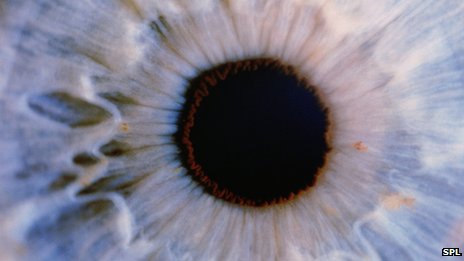

在試驗中,來自牛津大學的研究小組選擇了完全失明的老鼠作為研究對象。這些老鼠的視網(wǎng)膜中完全沒有感光細胞,無法判斷光明和黑暗。

在注入感光細胞后,研究人員不斷觀察這些老鼠能否感受到亮光,檢測在遇到亮光時它們的瞳孔是否會收縮,并用腦部掃描儀觀察老鼠的腦部是否處理視覺信息。結果顯示,接受試驗的老鼠在兩周后視力便有所恢復。